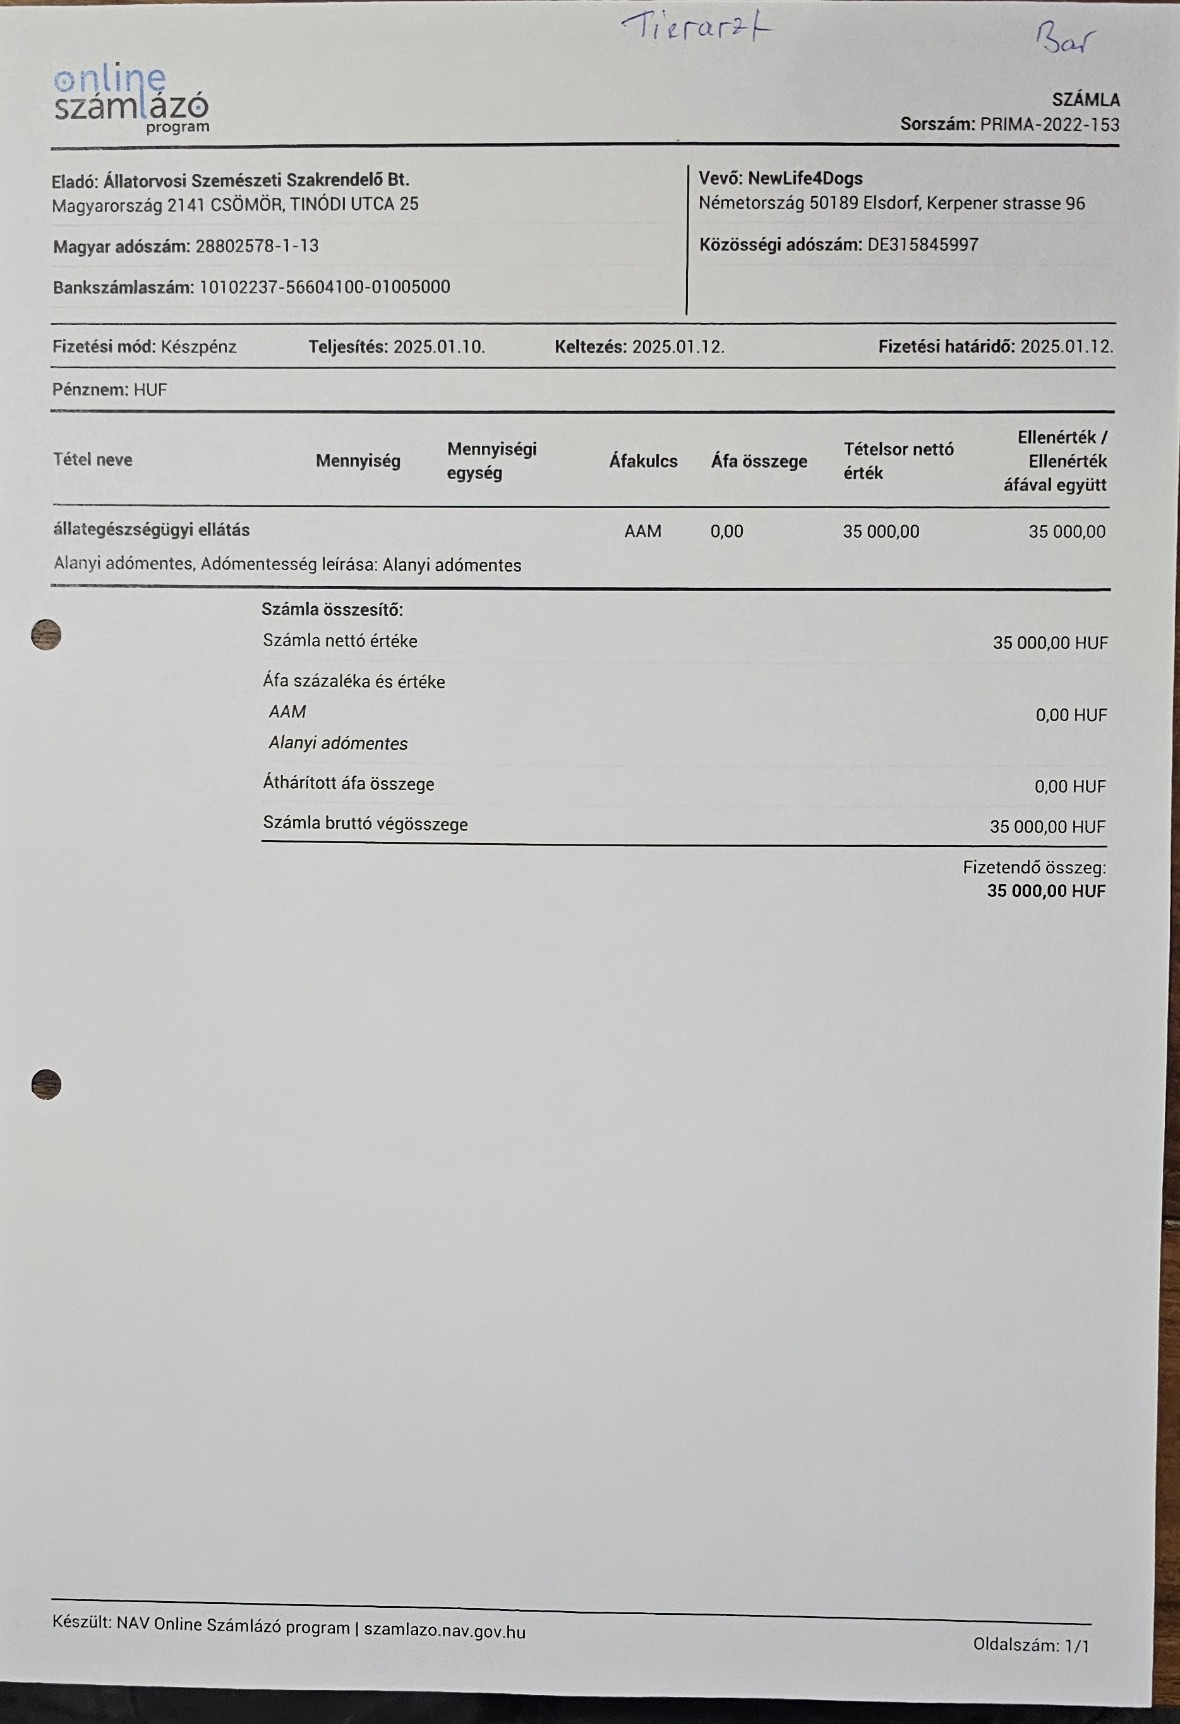

So zum Beispiel unsere kleine Stella, ein Welpen Mädchen das hier im Wald aufgefunden wurde. Nur 4 Tage nach Ankunft ging es Stella extrem schlecht und wir brachten sie in die Tierklinik zur stationären Aufnahme. Dort wurde sie intensivst medizinisch behandelt und musste 9 Tage in der Klinik verbleiben. Nur dieser eine Klinikaufenthalt verursachte Kosten in Höhe von 261.000,00 Forint ( ca. 640,00 Euro). Medikamente für die weitere Versorgung unserer Hunde musste bestellt werden. Ebenso Welpenfutter mussten wir nachkaufen. In den ersten Wochen wurden einige Hunde vergesellschaftet, damit die Quarantänestation wieder freie Zwinger hat. Denn in der Tötung warten Hunde darauf von uns abgeholt zu werden. Dies wird nun in den nächsten Tagen geschehen. Auch Klinikbesuche Kastrationen wurden wieder durchgeführt. Alleine hierfür betrug der finanzielle Aufwand ca. 750.000,00 (= ca. 1840,00 Euro) in der ersten Hälfte des Monats. Leider ist zur Zeit die Zeit extrem knapp, weswegen wir uns für die verspäteten Berichte entschuldigen. Doch die Rettungsaktionen und das Wohl unserer Schützlinge haben nun einmal Vorrang.

Auch hier in Örkény wurden wir zu einer schwerst verletzten Hündin gerufen. Blutüberströmt fanden wir die Hündin vor einem hiesigen Geschäft liegend auf. Der Inhaber des Geschäftes kümmerte sich bis zu unserer Ankunft um die Hündin, Da sie in ihrem Zustand und dem hohen Blutverlust die Fahrt bis zu Klinik nicht überstanden hätte ließen wir den hiesigen Tierarzt zu Notversorgung kommen. Die weitere Behandlung kann nun hier erfolgen und uns bleibt nur zu hoffen, das sie diese Verletzungen überleben wird. Natürlich werden wir auch für diese Hündin alles tun und unser bestes geben.